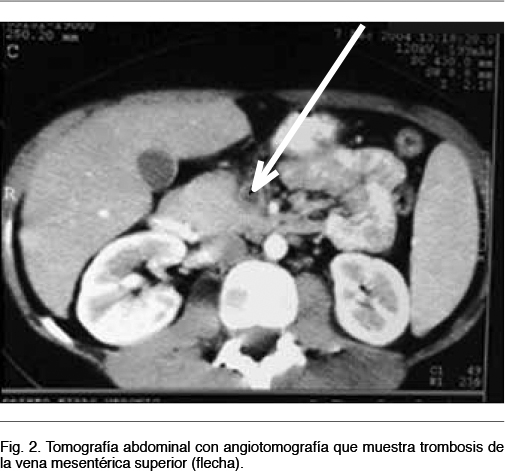

La angio-tomografía abdominal identifica dichas lesiones y evidencia trombosis de la vena porta y suprahepáticas, compatible con el diagnóstico de pileflebitis séptica (Figura 1 y 2).

Es de fundamental valor para el control evolutivo, pudiendo detecta recanalización o no del territorio portal, el desarrollo de cavernomatosis portal y signos de hipertensión portal. (7) La ecografía intraoperatoria es un método fiable para confirmar el diagnóstico y evaluar el grado de extensión de la trombosis. (12) La presencia de aire intraluminal indica enfermedad avanzada y es un elemento de mal pronóstico. La tomografía abdominal con angiotomografía es el estudio de elección, este revela la trombosis venosa porto-mesentérica, (Figura 2) mostrando un defecto en el relleno venoso con atenuación central, rodeado por el anillo de la pared venosa. Permite además evaluar la existencia de isquemia de la pared intestinal con una sensibilidad mayor al 90% y defectos de la circulación porto-mesentérica. (8,13) En el caso analizado el parénquima hepático mostró a nivel del lóbulo derecho áreas hipodensas con zonas hiperdensas mal definidas, con desplazamiento de vasos y periferia hipervascular compatible con abscesos múltiples. Además pueden coexistir microabscesos (no visualizables por esta técnica) y que por su tamaño no es posible drenar. (14)

La pileflebitis se sospecha por la clínica y se confirma con estudios imagenológicos, siendo la angiotomografía abdominal el método de elección. El diagnóstico y tratamiento oportunos de esta entidad, disminuyen las complicaciones y la mortalidad. El mismo consiste en antibióticos de amplio espectro, por períodos prolongados. Los abscesos hepáticos requieren drenaje quirúrgico o percutáneo. La anticoagulación es controversial y debe individualizarse su indicación.